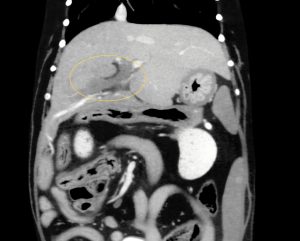

頻回の嘔吐と食欲不振を訴えて病院に来られたワンちゃん、血液検査で肝酵素と炎症マーカーの重度上昇があり、以前から胆嚢粘液嚢腫を抱えていたため、破裂などを疑わせる状況でした。超音波検査とCT検査では、胆嚢周囲の炎症、総胆管と肝内胆管の肥厚が見られましたが、破裂や閉塞所見は認めませんでした。胆嚢破裂や閉塞がない状態で、このような劇的な症状が起きることは比較的珍しいと思います。しかし、胆嚢粘液嚢腫が病態に関与していることは間違いなかったため、飼い主様に同意してもらい、その日のうちに胆嚢摘出術を行いました。

↑胆嚢周囲(鎌状間膜)の炎症所見